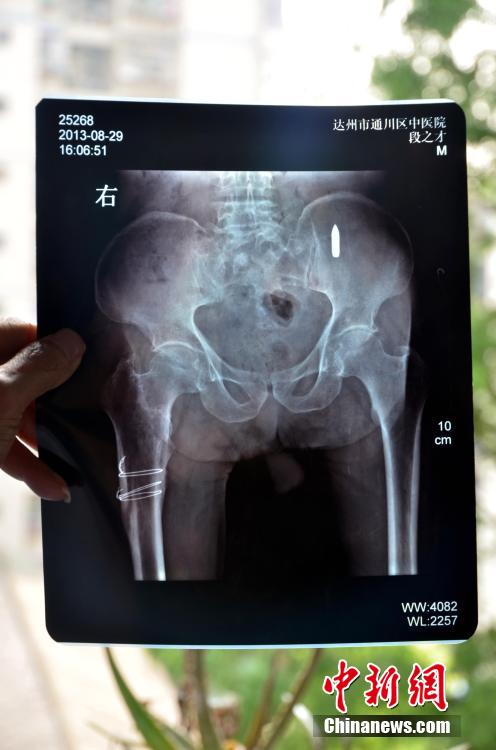

11 ????? 2015/????? ????? ??????? ???????/???? ?? ?????? ???? ??? ???? ???? 94 ???? ???? ??? ???? ???? X ???? ???? ?? ?? ????????? ????? ?????? ???? ????? ?? ?????? ??????.